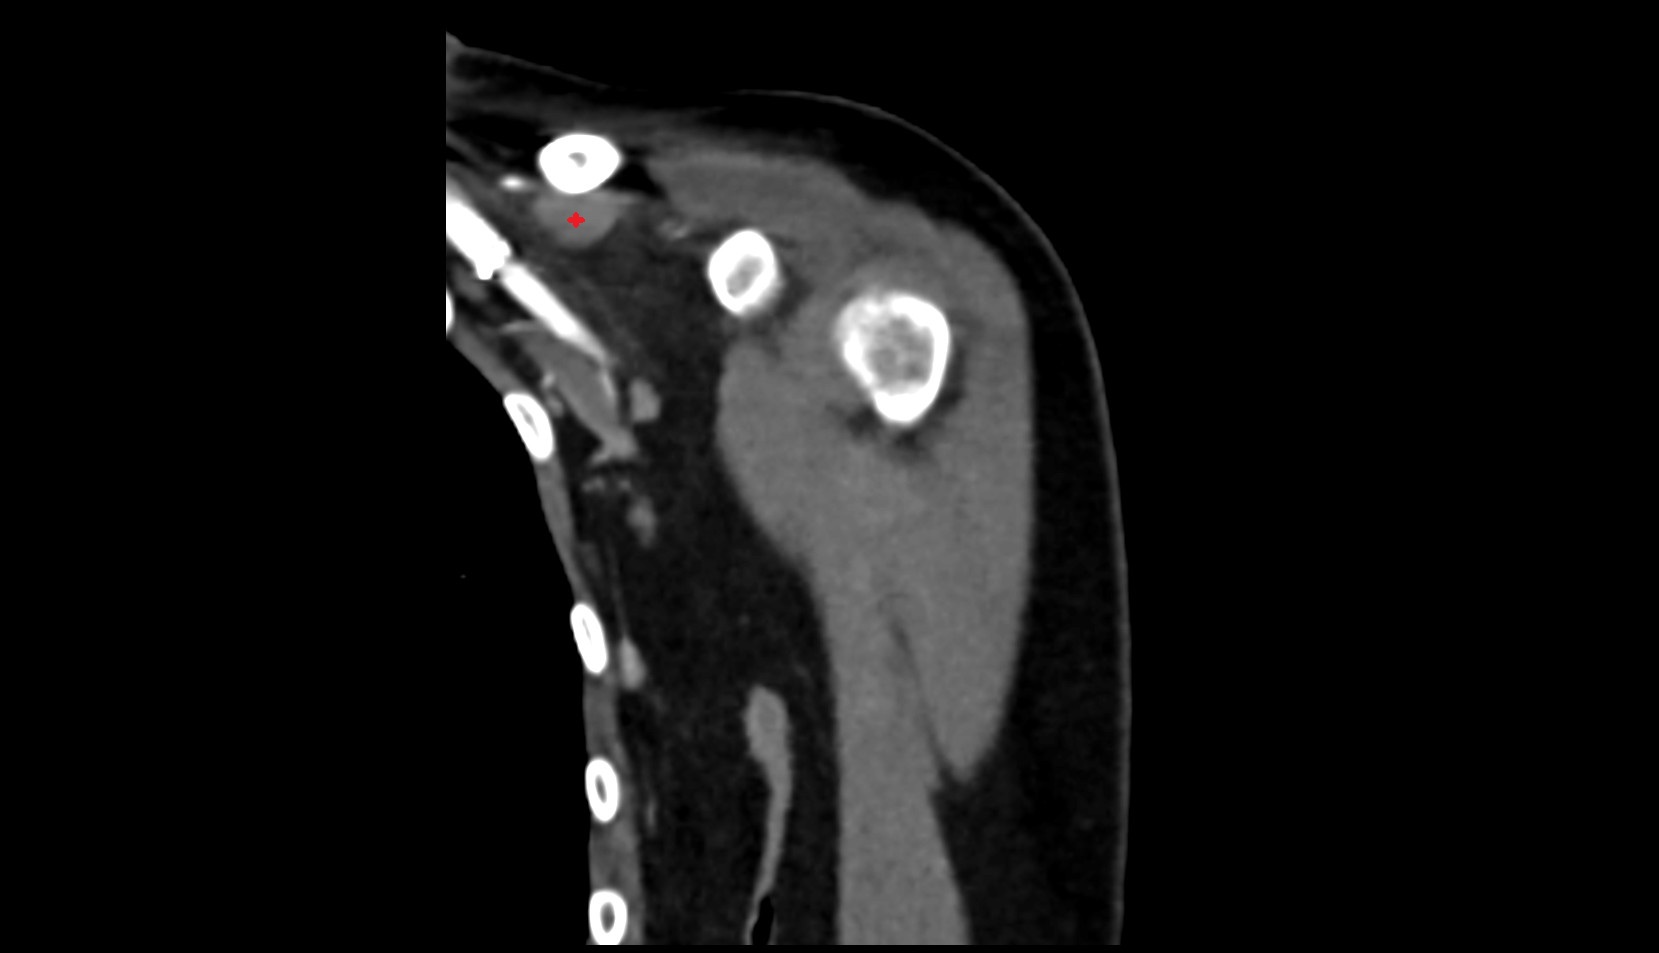

- Glenoid fossa

- Glenoid process of scapula

- Spine of scapula

- Acromion process of scapula

- Coracoid process of scapula

- Scapular body

- Humerus

- Head of humerus

- Shoulder joint (glenohumeral joint)

- Adipose tissue (Shoulder)

- Subacromial space